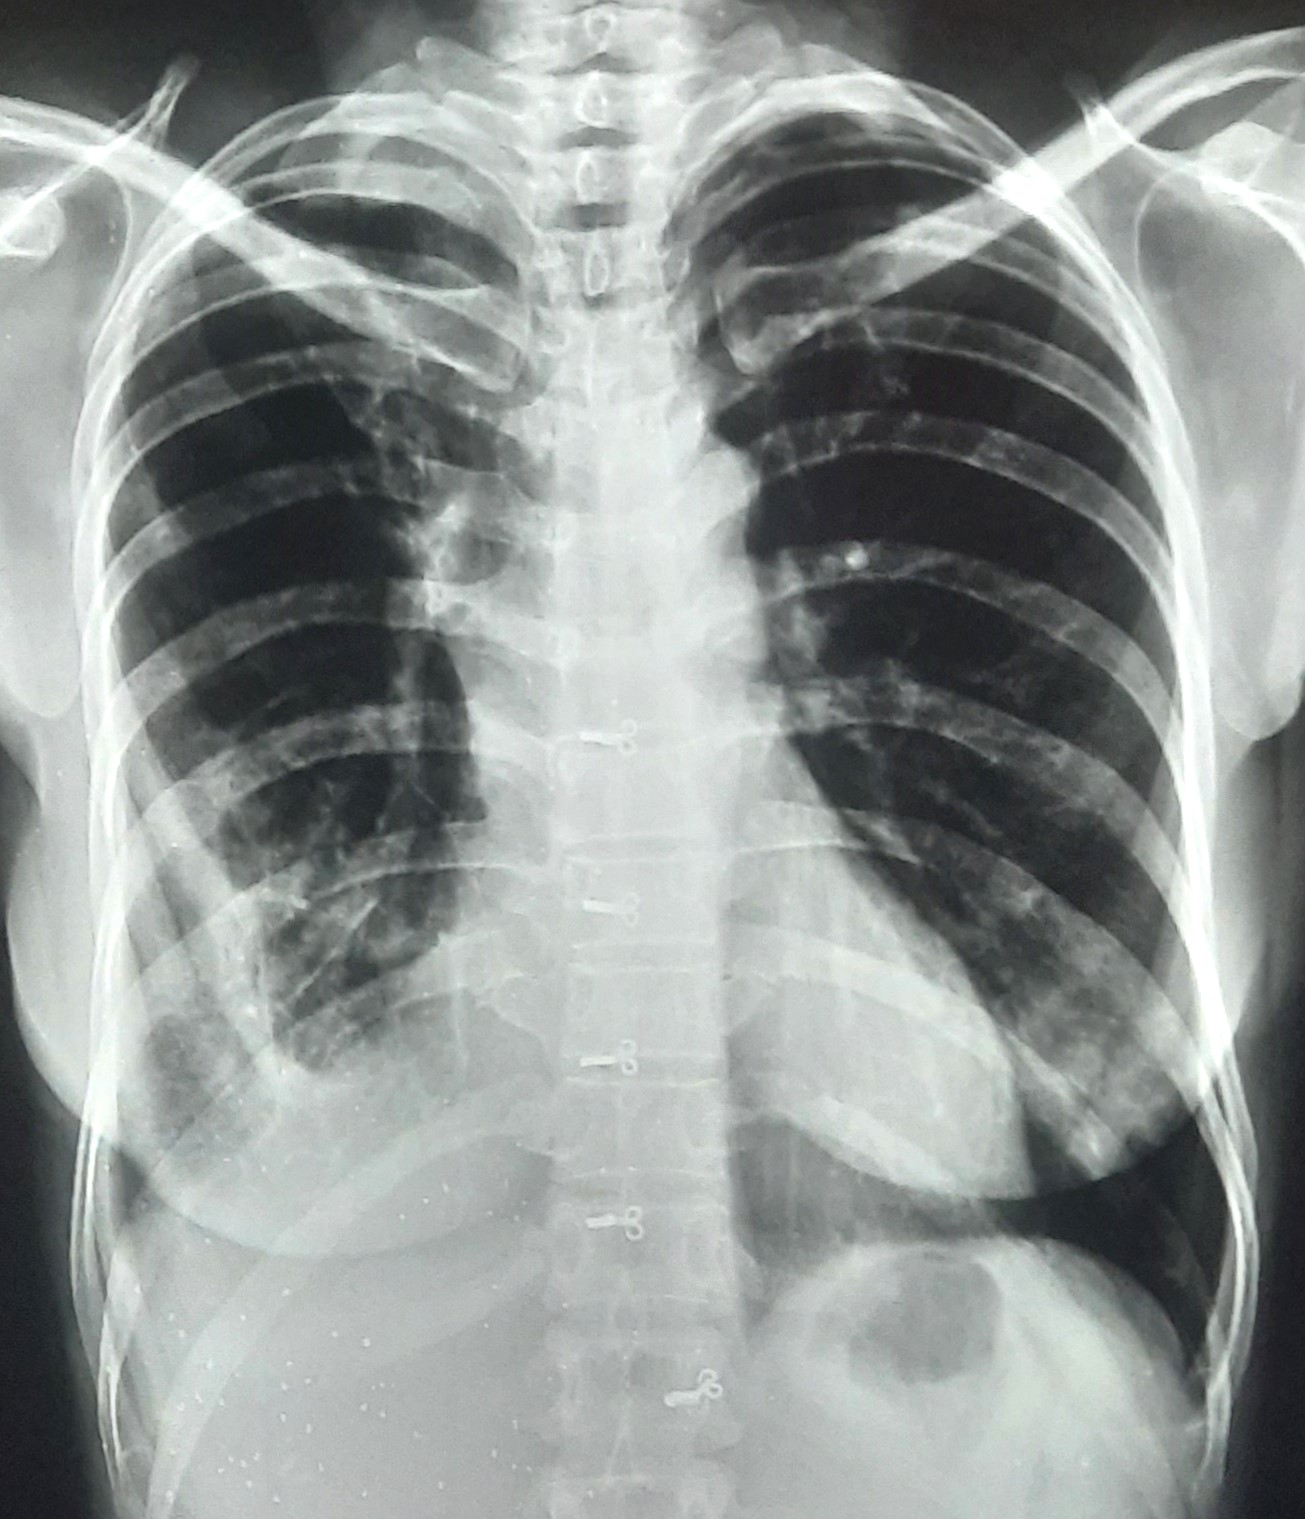

| 206 | IGGMC, Nagpur, Nagpur | P2 | 29-4266 | SHUBHAM URKUDE | Consent taken on Paper | 30 Yrs. |

Provisional Diag : PTB?

Final Diag : CLINICALLY DIAGNOSED PTB WITH OLD EPTB WITH LOSS TO FOLLOW UP IN CHRONIC ALCOHOLIC |

TB Case (Confirmed) | BILATERAL MIDDLE ZONE HAZZINESS/CONSOLIDATION | Abnormality visible on x-ray |